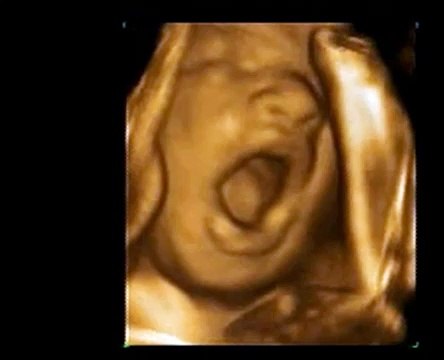

Baby Yawns in Womb - 4D Ultrasound Video Footage